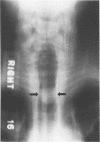

The case history is presented of a patient with a tracheal schwannoma who remains free of disease five and a half years after laser resection. This illustrates the potential of this approach in the management of tracheal schwannoma.